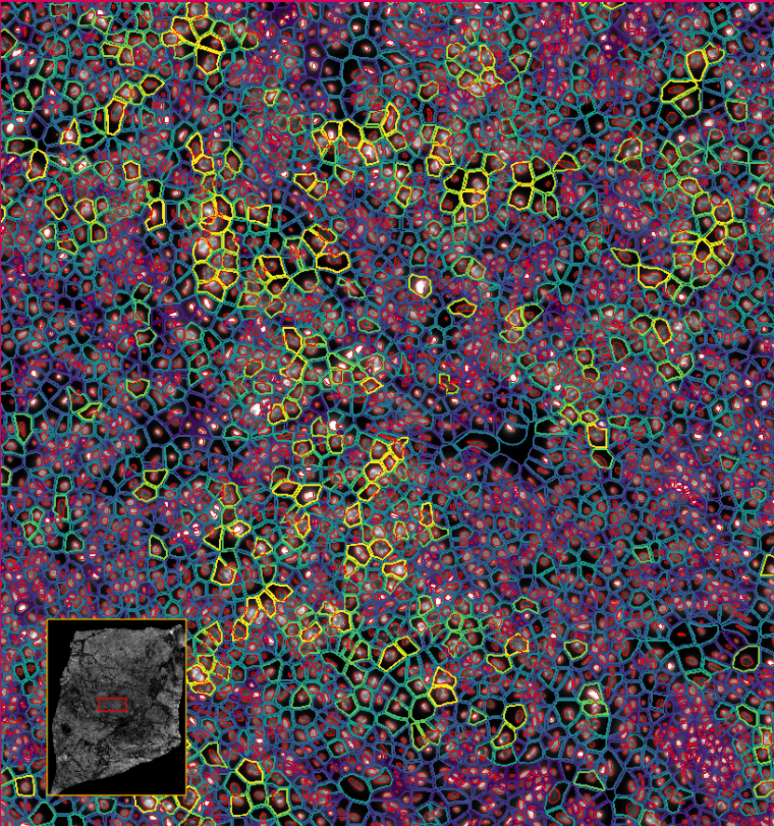

ͼ4-1£ºÀûÓÃDAPI¶Ôϸ°ûºËȾɫ£¬½áºÏÉî¶È½ø½¨²½Öè´§¶ÈÆëÈ«µÄϸ°ûÌìǵ

ͼ4-2£ºÀûÓÃDAPI¶Ôϸ°ûºËȾɫ£¬½áºÏÉî¶È½ø½¨²½Öè´§¶ÈÆëÈ«µÄϸ°ûÌìǵ